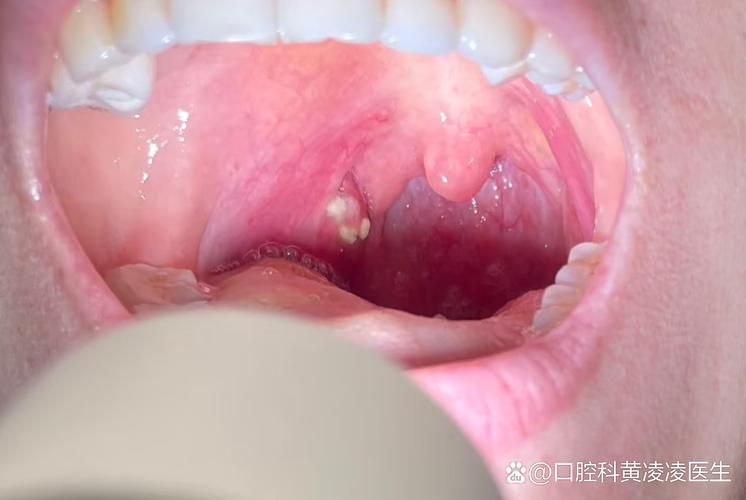

下面我们来分析一下口腔两侧白色颗粒的几种常见可能性:

粘膜下腺体(Fordyce spots / 福代斯斑)

这是最常见的原因之一。

- 外观:看起来是针头大小、淡黄色或白色的扁平或略微凸起的小颗粒,像小米粒一样,它们是皮脂腺的异位,也就是在口腔粘膜(本不该有皮脂腺的地方)出现了皮脂腺。

- 特点:

- 通常对称地出现在双侧颊粘膜(也就是口腔两侧)。

- 无痛、无不适感。

- 表面光滑,用手触摸可以感觉到。

- 可能长期存在,大小和数量不会明显变化。

- 处理:完全正常的生理现象,不是疾病,无需治疗。